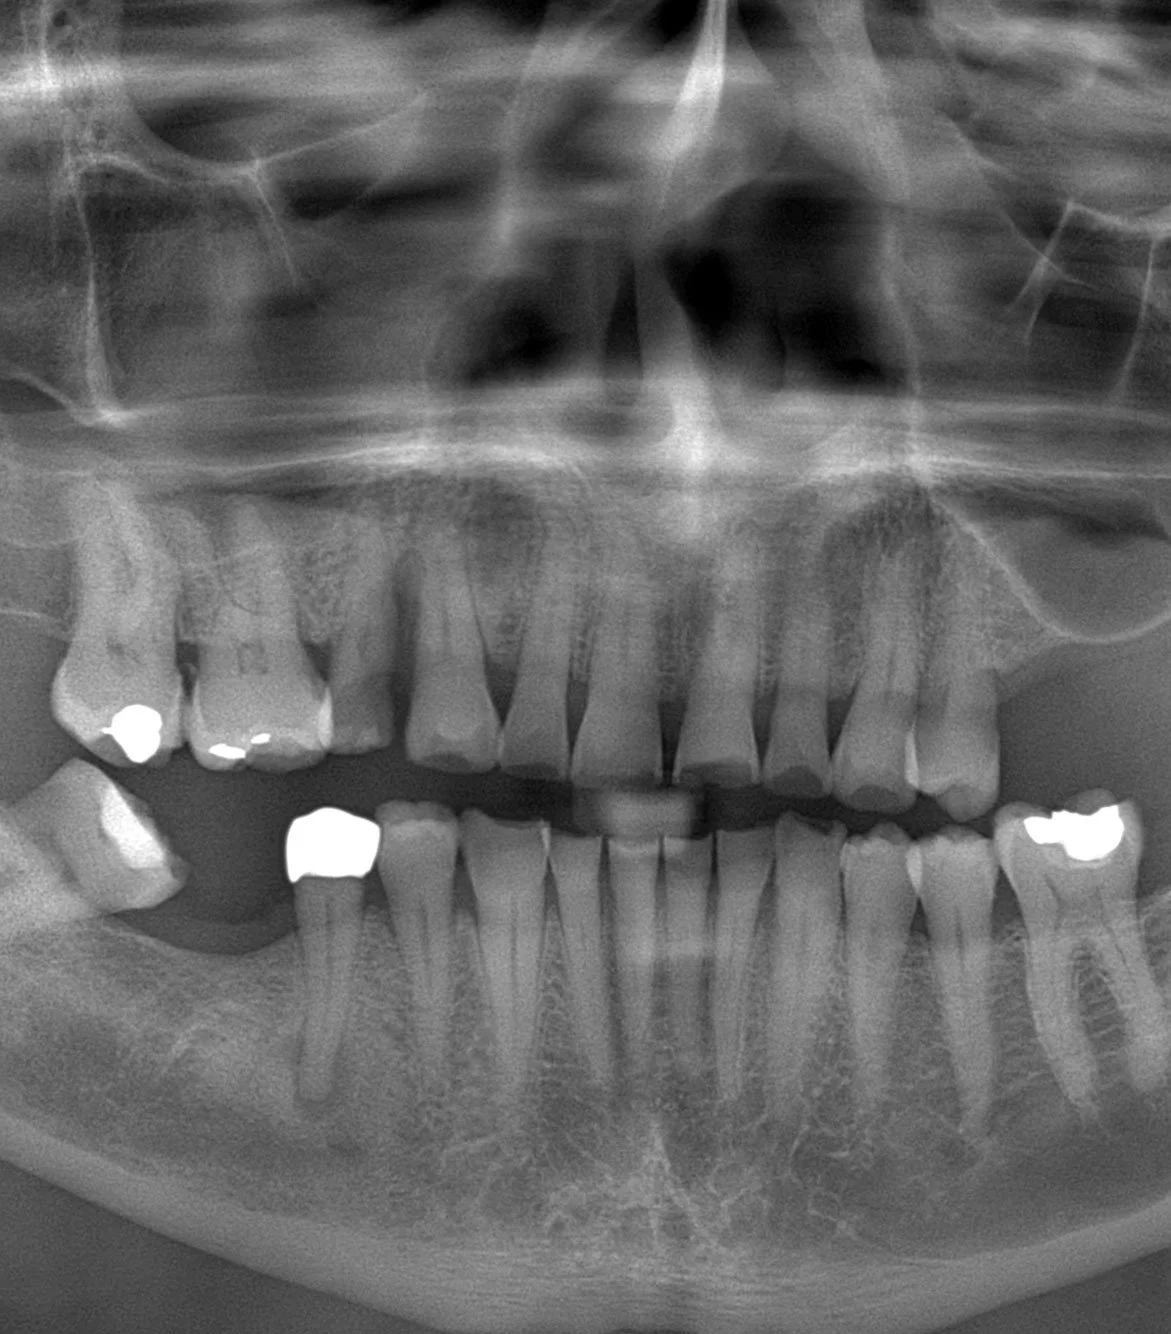

Segundo paso: Radiografías

Solicitamos una radiografía panorámica para evaluar el estado general de los maxilares, dientes remanentes y estructuras anatómicas relevantes. Este examen nos entrega una visión global que ayuda a planificar correctamente el tratamiento.